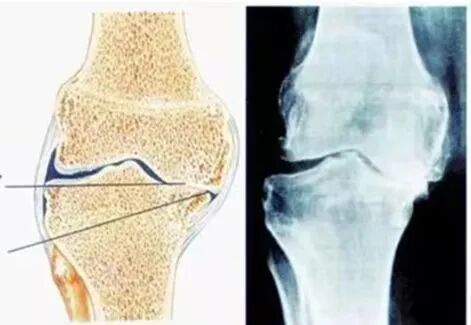

发表时间:2023-06-02 15:51 膝关节骨性关节炎(OA)又称退行性骨关节病,属于关节提前老化,特别是关节软骨老化,是一种由于关节软骨退行性变,引起的关节软骨完整性破坏及关节边缘软骨下骨板病变,继而导致关节症状和体征的一组慢性退行性关节疾病,被认为是一种慢性疾病会使患者关节疼痛、僵直畸形、功能障碍,多见于中老年人。 骨性关节炎是最常见的关节炎形式。最早体现在手的小关节,它是一种影响关节所有组织的疾病,包括软骨,骨骼,韧带和肌肉。但最常见的是影响膝关节、髋关节、脊柱、手等部位,其中膝关节炎占41%。好发年龄通常在 50 岁之后,如果有关节损伤,发生会更早开始。它会干扰患者对生活的享受,尤其是喜欢户外运动的。膝关节是最常见的下肢关节。患有骨性关节炎的人在进行常规活动(例如步行和上下楼梯)时经常会出现膝盖疼痛。 ![]() 根据骨关节炎累计部位,分为内侧侧室、外侧间室、髌股间室骨关节炎。在膝关节骨性关节炎中,导致骨骼(股骨和胫骨)、关节和软组织发生病理改变,从而导致疼痛,关节僵硬,关节活动度减少,步态异常和肢体不等长,继而累及髋和踝关节,甚至腰椎疾病。下肢负重轴线(内翻畸形、外翻畸形、旋转畸形、短缩畸形、侧方移位畸形和复合畸形)异常会出现什么情况呢? 下图显示当对线异常的时候,内侧负荷增加,软骨磨损,导致膝关节疼痛。 ![]() OA被认为是一种慢性疾病,老年膝关节疼痛在临床上非常常见,传统治疗手段有非手术和手术治疗,后者典型代表是膝关节表面置换手术,解除病人疼痛,恢复行走功能,但术后满意仅有82%,术后不能获得较高的运动能力和关节屈伸活动能力。 ![]() 临床表现: